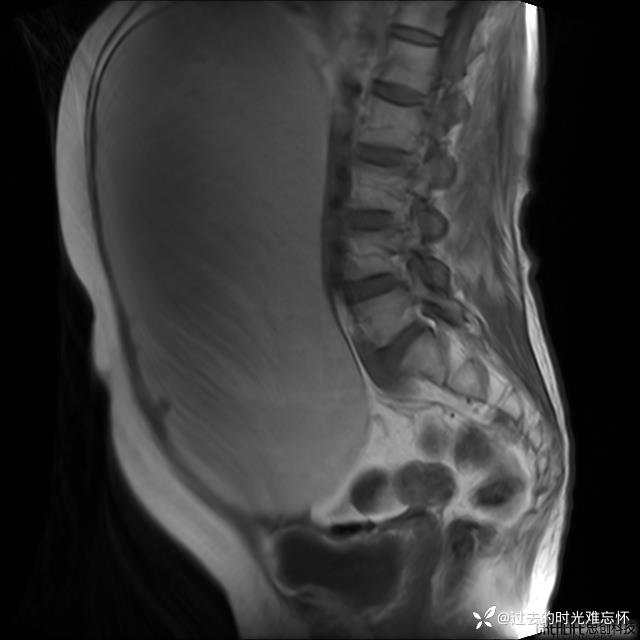

患者性别:女

患者年龄:65岁

主诉: 发现腹部隆起半年余。无其他明显不适。

浆液性囊腺瘤 (22)